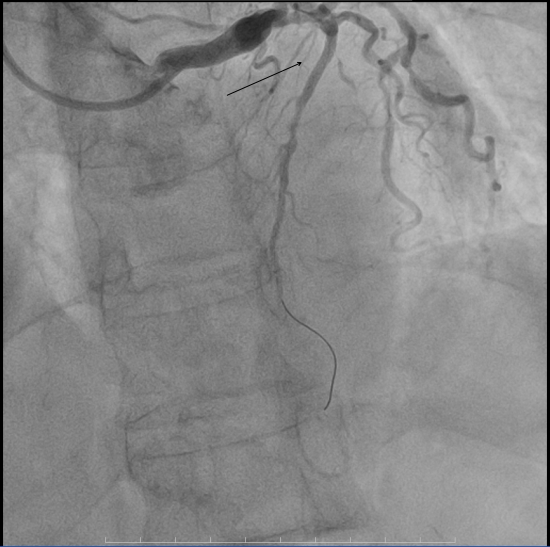

术前心电图呈现出与该病症相符的典型特征。入院后急诊冠脉造影显示,前降支近中段于第二对角支发出前后节段性病变,最重狭窄程度高达98%,情况危急万分。但我院介入团队凭借丰富的临床经验和娴熟的操作技术,顺利引导导丝通过病变部位,随即开展球囊扩张操作,而后精准植入一枚2.75*18mm支架。术后造影结果令人满意,患者的心肌供血状况得到显著改善,为后续康复奠定了坚实基础。

▲术前冠脉造影